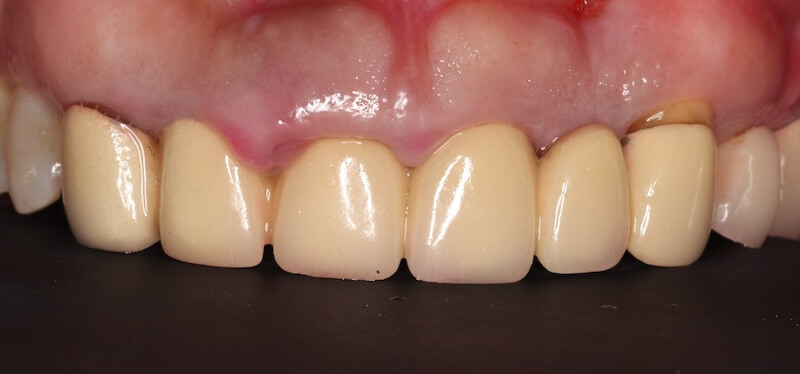

在這個相對健康的牙周環境狀態下,我們利用DSD數位微笑設計,全數位化的口內掃描並製作出第二組臨時假牙,透過這組假牙置放在口內和她討論未來正式假牙的外型與顏色。

手術完成後的兩三個月左右,製作正式的假牙。最終的假牙我們設計成兩組正中門牙和犬齒相連的牙橋,和原來六顆連在ㄧ起的設計相比,清潔會相對容易很多。Ms.H 對治療前後的明顯感受是:牙齦牙周的問題獲得滿意的解決以外,新的假牙的美觀度也有大幅的改善,花時間好好投資在自己身上,非常值得。未來規律定期回診好好的維護,相信能夠常保健康穩定的治療成果。